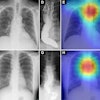

All of the labeled x-rays were randomly split into development and testing sets at the patient level and based on stratification, with the trained algorithm then evaluated on the testing set using quantitative metrics and visual evaluation techniques.

According to the findings, the algorithm perfectly classified the laterality (F1 scores of 100% on the testing set). When classifying the imaging projection, the algorithm achieved F1 scores of 99.2% on anterior-posterior views, 100% on axillary views, and 100% on lateral views.

In addition, when classifying the implant type, the model achieved F1 scores of 100% on preoperative images, 95.2% on aTSA, and 100% on RSA x-rays.